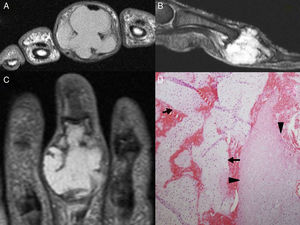

The patient was an 82-year-old man diagnosed with gout. He presented with a tumor-like lesion on the second phalanx of the third finger of the left hand that had developed months earlier (Fig. 1A and B). Since a gouty tophus at that site is rare, he underwent plain radiography (Fig. 1C and D), which showed an expansile lytic lesion. The findings in magnetic resonance imaging (MRI) were suggestive of malignancy (Fig. 2A–C). Ultimately, biopsy was performed, leading to a diagnosis of enchondroma (Fig. 2D).

(A–C) Magnetic resonance images; multilobulated expansile lesion, with endosteal scalloping and substantial cortical thinning, which is hypointense in T1 (axial plane) and hyperintense in the T2-weighted sequence with fat suppression (sagittal plane) and in a short tau inversion recovery (STIR) sequence (coronal plane). (D) Biopsy of the tumor showing mature hyaline cartilage (arrows), with areas of myxoid degeneration (arrowheads), compatible with enchondroma.